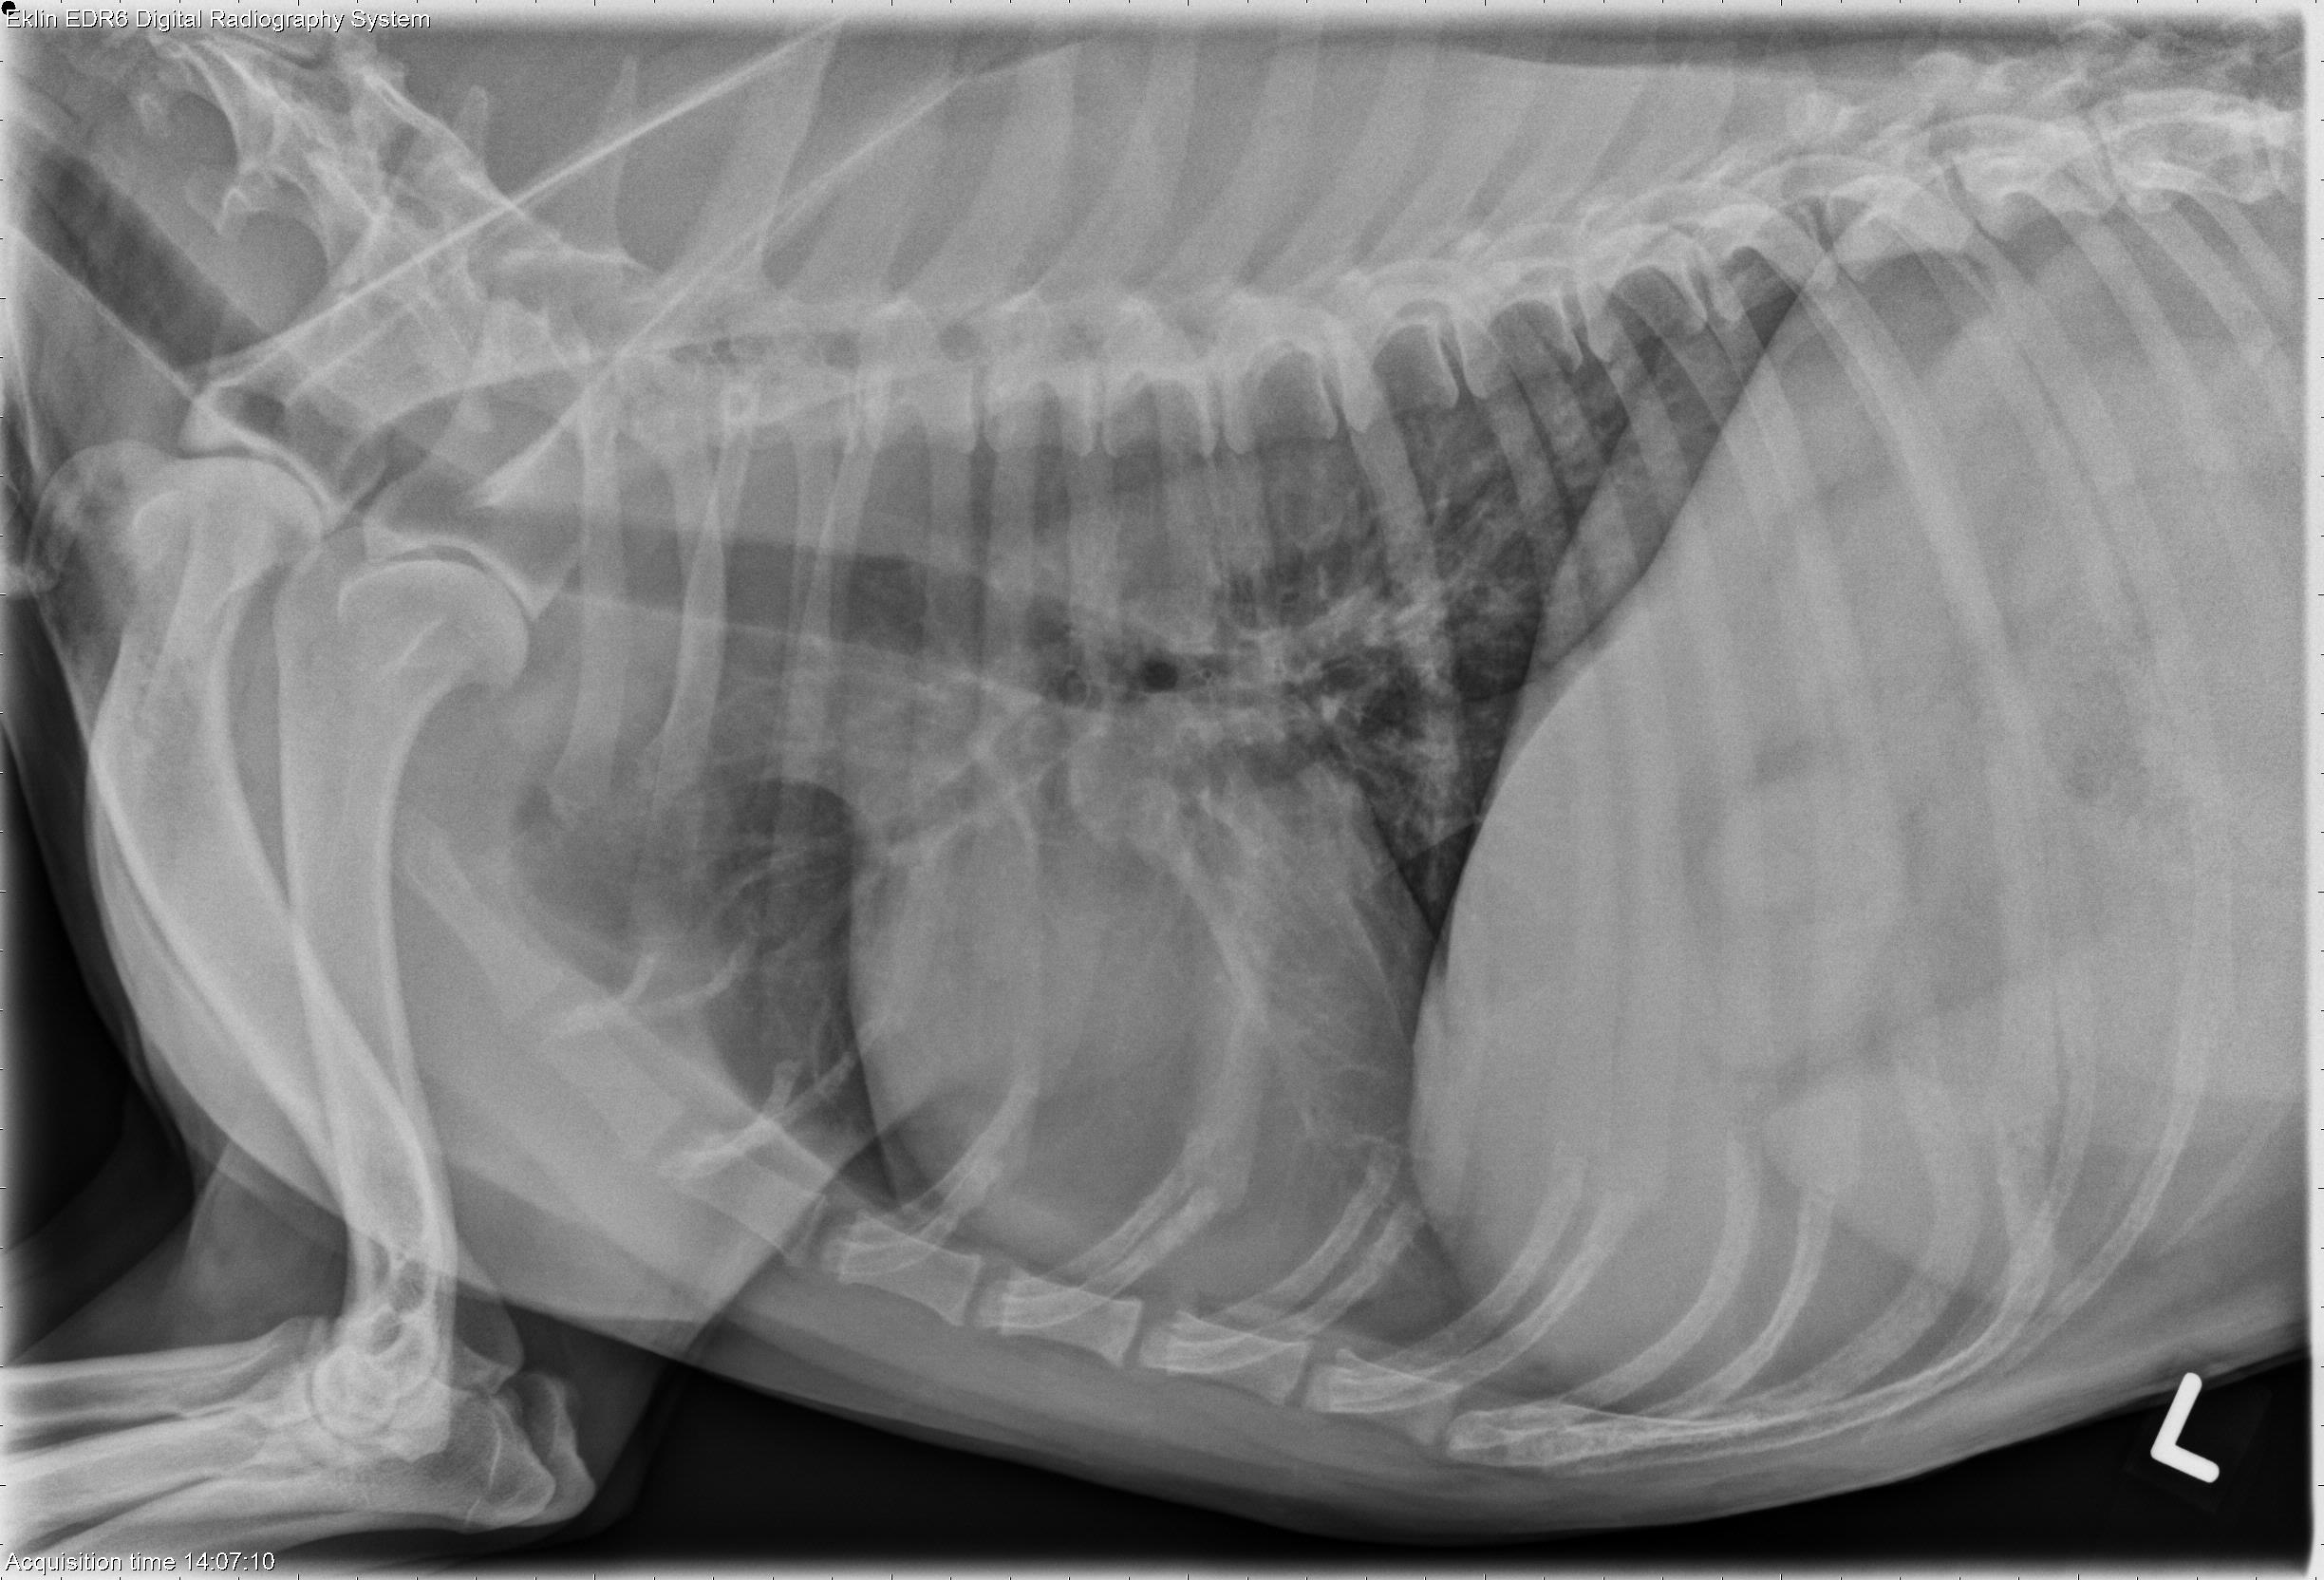

This week’s case is an 11-year-old Beagle with right thoracic limb lameness. How would you describe this lesion?

R LAT Thorax

L LAT Thorax

DV Thorax

There is geographic lysis of the proximal humeral metaphysis with irregularity of the lateral cortex on the craniocaudal projection. There is a more well-circumscribed round radiolucencly proximally which is consistent with the site of previous bone biopsy. The thoracic radiographs are within normal limits.

Aggressive bone lesion of the right proximal humerus may be due to primary bone neoplasia, fungal osteomyelitis, or metastatic disease.

• Metastatic hemangiosarcoma

A splenic mass was found on abdominal ultrasound. Resection of the mass was performed, and hemangiosarcoma was found on histopathology. Right thoracic limb amputation was also performed, and the humeral lesion was found to be metastatic hemangiosarcoma.